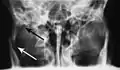

Plain film radiography

Traditionally, plain films of the mandible would be exposed but had lower sensitivity and specificity owing to overlap of structures. Views included AP (for parasymphsis), lateral oblique (body, ramus, angle, coronoid process) and Towne's (condyle) views. Condylar fractures can be especially difficult to identify, depending on the direction of condylar displacement or dislocation so multiple views of it are usually examined with two views at perpendicular angles.[11]

Towne's view of a bilateral condyle fracture. White arrow is a fracture on the neck of the condyle. Black arrow shows the condyle pulled to the medial. The same injury can be seen on the opposite side